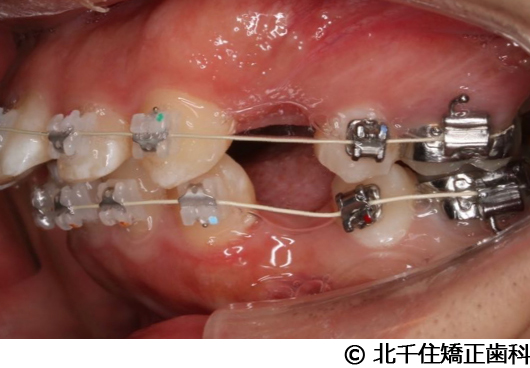

【症例2】上顎前突症

- 治療前

- 治療中

- 治療後

- 治療名

- 上顎前突症

- 費用

- 1,399,000円(税込)

- 期間

- 3年6ヵ月

- 治療回数

- 42回

- 通院頻度

- 1ヵ月ごと

- 年齢・性別

- 19歳10ヵ月・男性(初診時)

主訴:出っ歯、口元の突出、横顔をきれいにしたい

骨格性の上顎前突、上下顎第一小臼歯4本及び上顎第二大臼歯を抜歯して矯正用アンカースクリューを併用してワイヤー矯正治療(セラミックブラケット)。

骨格性上顎前突に対し、抜歯および矯正用アンカースクリューを併用した矯正治療により歯列および咬合関係の調整を行った症例である。治療後は保定装置を使用し、歯列および咬合の安定維持を目的として定期的な経過観察を行っている。

※治療結果は個人差があります。

治療を行う上での注意点(リスク・副作用)

歯磨き不良に伴うカリエスや歯周病、顎関節症、歯根吸収など。